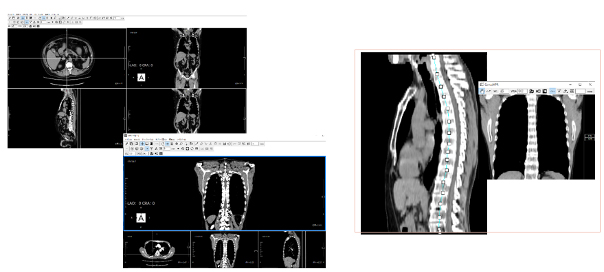

画像形態認識によるスライス位置合わせ

今回検査と過去検査の比較読影において,スライス位置を合わせる作業は煩雑になりがちですが,EV Insite Rでは画像の形態情報を基にスライス位置を自動で合わせることが可能です。CTとMR,フットファースト,ヘッドファーストなどの条件が異なっていても対応が可能です。

特長〈2〉

MPR

ビューアからワンクリックで高速にMPR作成が可能です。血管走行の確認などにおいてはCurved MPRの作成も行えますので,任意の角度での画像観察が可能です。